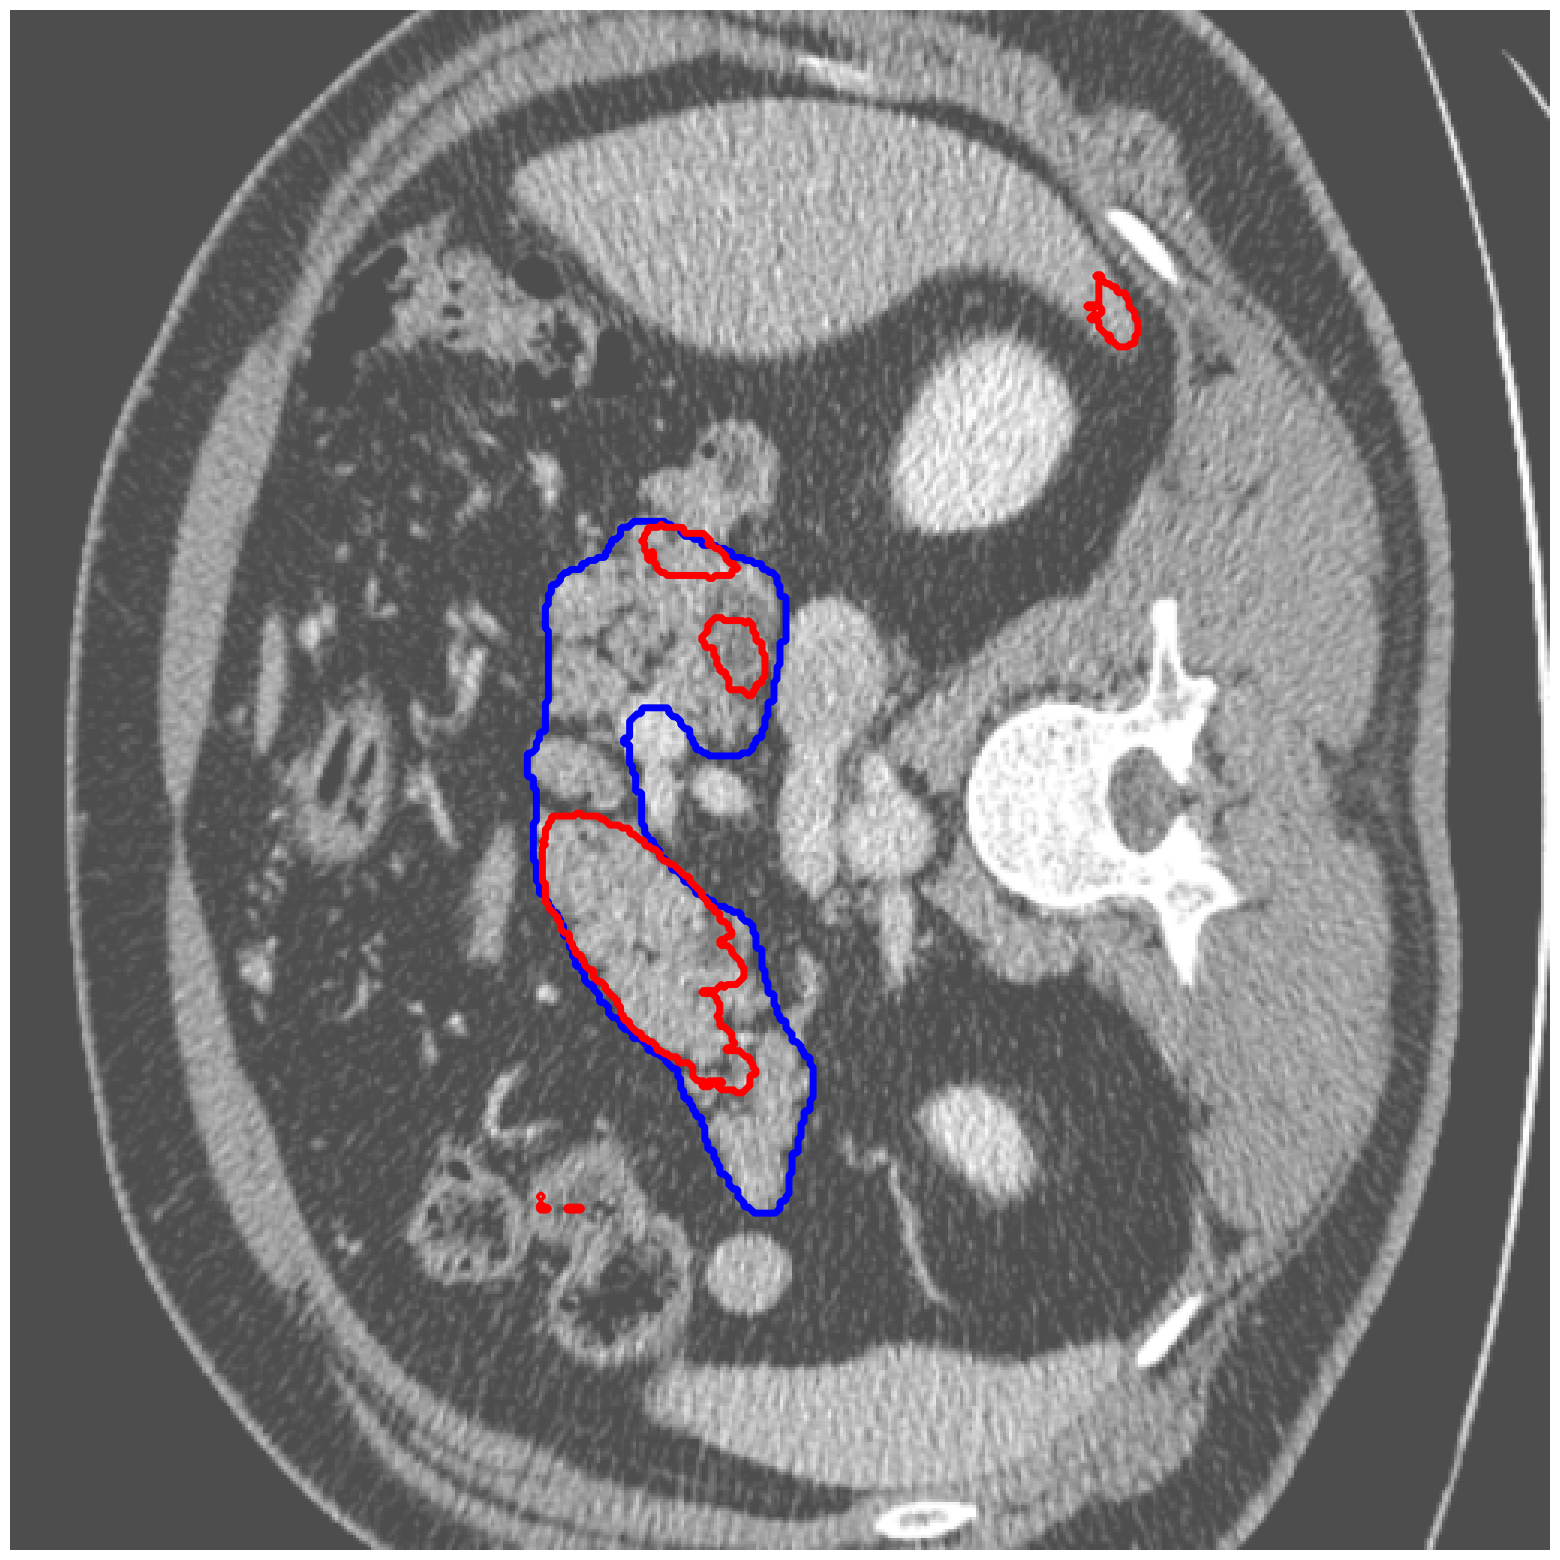

|

MSD-Pancreas |

![]() |

| (a) Original pred. | b) Consema | ——— c) Standard CRC ——— | ——— d) RW-CP (Ours) ——— | |||

Visually, we observe in Fig. 1 that RW-CP is able to produce prediction sets much closer to the ground-truth than standard CRC or Consema. Our approach is even able to remove small over-segmentated areas, whereas methods such as Consema can only increase the size of the prediction set, even when the segmentation model produced false positives.

We hypothesize that the performance of RW-CP stems from its pre-processing step on probabilities, which mitigates the overconfidence commonly observed in deep learning segmentation models [16]. Their raw softmax probabilities are often skewed towards either 0 or 1 (see Fig. 1.c). This overconfidence compresses the effective range of possible values for the empirical threshold used in Conformal Risk Control, making the final prediction mask extremely sensitive to small fluctuations in . On the contrary, by first applying a diffusion process, the pixel-wise probabilities become more varied and less polarized (as shown in Fig. 1.d). This broadened distribution stabilizes the empirical during calibration, leading to a more robust and tighter prediction set, which translates to better overall segmentation metrics